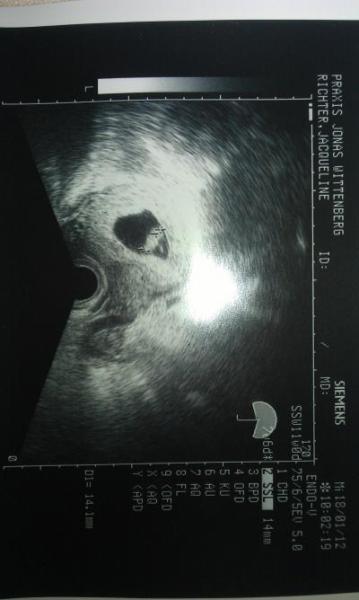

Termin war toll....alles nun zeitgerecht et 30.08. Bildchen ist bei und Herzchen hat geschlagen...in 4wochen wieder hin....sau glücklich gerade... 7+6 bin ich

Bild zu ich bleibe bei euch - Forum für August - Mamis